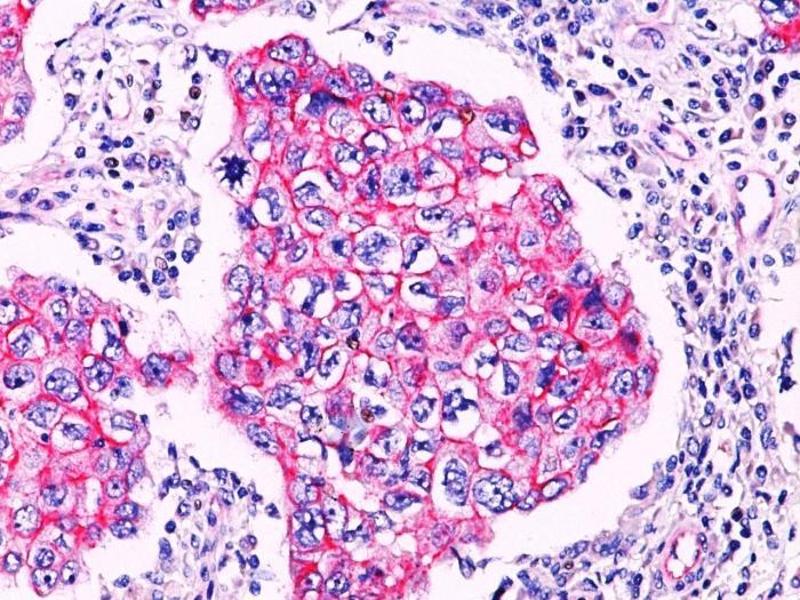

Choisissez l’un des 247 anticorps CTNNB1 de notre liste de produits basés sur 68 publications et 314 images de validation.

Découvrez des anticorps CTNNB1 fiables issus d’une large sélection de fabricants renommés. Notre portefeuille permet une détection précise de CTNNB1 dans plusieurs espèces, y compris Human, Mouse, Rat, Dog, Monkey, Chicken, Cow, Zebrafish (Danio rerio), Pig, Horse, Rabbit, Xenopus laevis, Hamster, Bat, Guinea Pig, Sheep, Opossum, et prend en charge diverses applications de recherche telles que WB, IHC, ELISA, IF, FACS.